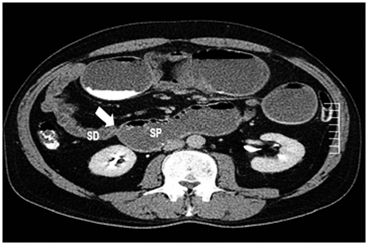

Por esta sintomatología, se le practicó una TC abdómino-pélvica con contraste una semana antes en otra institución, en la cual se informó dilatación de la cámara gástrica, duodeno y yeyuno proximal, con cambio de calibre abrupto a ese nivel, sin evidencia de otros hallazgos (figuras 1 y 2).

Por esto, se utiliza más la tomografía computadorizada (TC), pues es muy sensible para detectar el tumor primario. Se observa generalmente como una lesión focal, irregular, estenosante, con engrosamiento mural, heterogénea, con realce en la fase contrastada y que, en ocasiones, puede disminuir la luz e incluso causar obstrucción intestinal; algunas veces se pueden observar lesiones ulceradas o polipoides. Además, la TC es útil para evaluar la extensión tumoral local y a distancia; las metástasis son más frecuentes en el hígado y se manifiestan como lesiones hipodensas con buen realce en la fase portal 21,22.